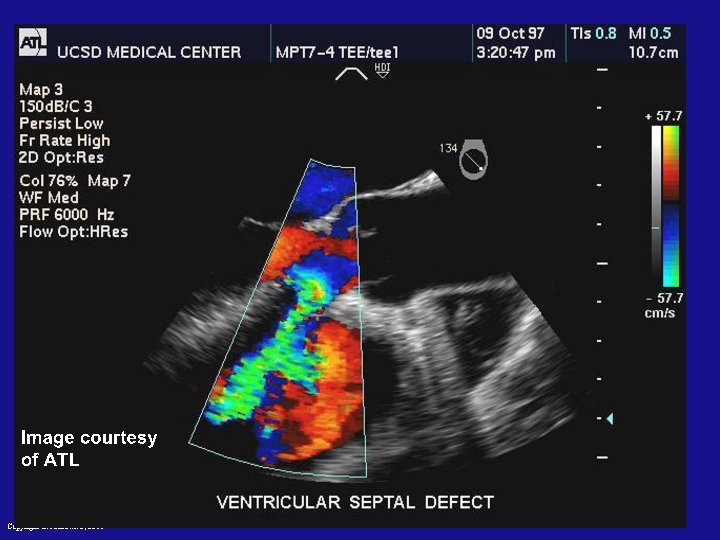

Ultrasound imaging Copyright L. Joskowicz, 2011

Ultrasound: principle • Probe sends high-frequency (1 – 5 Mhz) sound waves into body • Sound waves travel into tissue and get reflected by boundaries • Reflected waves recorded by probe • Time of flight gives spatial info of the boundaries • Frequency of signal depends on a tradeoff resolution versus attenuation Copyright L. Joskowicz, 2011

Ultrasound imaging: characteristics • No radiation • Poor resolution (1 mm) nonuniform, distortion, noise • Low penetration properties • One 2 D slice or several slices (2. 5 D) • Relatively cheap and easy to use • Preoperative and intraoperative use Copyright L. Joskowicz, 2011